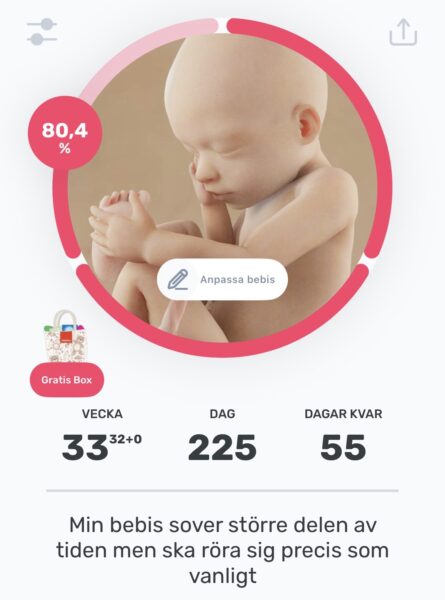

Idag hade vi återbesök på Crocus ultraljud för att försöka få bättre 3D bilder från lillan i magen… men dagens bilder blev ännu sämre än förra veckan tyvärr.

55 dagar kvar enligt beräknad förlossning!